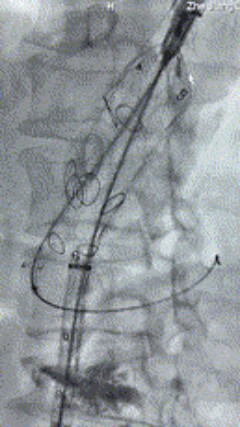

3. 经右股动脉导入超硬导丝,然后导入先健G-Branch 胸腹主动脉主体覆膜支架TAAA3418120e7i1010 一枚,释放主体支架至内分支打开,然后经左侧肱动脉入路,抓捕预置导丝成功后,将长鞘进入内分支出口处。

4. 经长鞘导入导管后,超选入腹腔干动脉,送入先健覆膜支架10*80mm一枚,近端重叠内分支,远端重叠腹腔干动脉,并予以10mm球囊后扩,手推造影显影良好。

5. 撤出腹腔干导丝导管,经左肱动脉长鞘继续抓捕预置导丝将长鞘超选至另一侧内分支,后超选进肠系膜上动脉,沿导丝送入先健覆膜支架10*100mm一枚,近端重叠内分支,远端重叠于肠系膜上动脉,并予以10mm球囊后扩,手推造影显影良好。